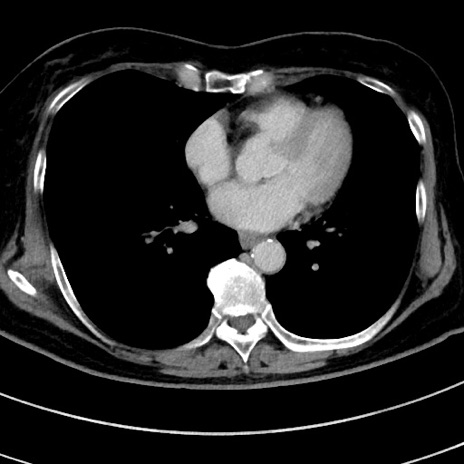

症例9(横断像)

【症例】 60歳代女性

【主訴】むかつき、みぞおちの痛み

【現病歴】3日前よりむかつきがあり、食事がとれない。

【既往歴】糖尿病

【身体所見】発熱なし、心窩部圧痛軽度あるも、腹膜刺激症状なし。

【データ】WBC 7400、CRP 1.92